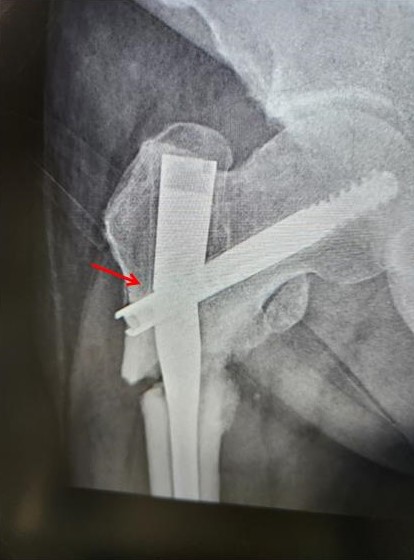

- 不癒合處血液供應不良:如果沒有血流,就不會有血小板製造成骨細胞,促進愈合,通常是因為纖維組織的生長至骨折處阻擋造成血流減少或植入不具有血流的鈣粉。(圖2)

Second, the blood supply to the non-union site is inadequate. Without blood flow, there will be no platelets to produce osteoblasts to promote healing (see Figure 2). Bone nonunion is often caused by fibrous tissue obstruction or the implantation of calcium powder without blood flow that blocks healing.

(圖二) 植入骨粉,骨粉沒有血液供應,會阻礙血流通過產生不癒合